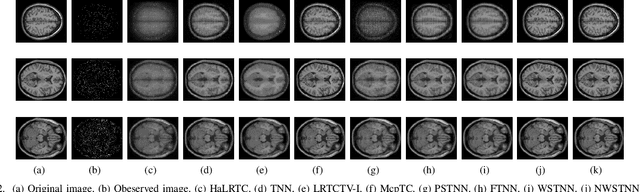

Abstract:Non-convex relaxation methods have been widely used in tensor recovery problems, and compared with convex relaxation methods, can achieve better recovery results. In this paper, a new non-convex function, Minimax Logarithmic Concave Penalty (MLCP) function, is proposed, and some of its intrinsic properties are analyzed, among which it is interesting to find that the Logarithmic function is an upper bound of the MLCP function. The proposed function is generalized to tensor cases, yielding tensor MLCP and weighted tensor $L\gamma$-norm. Consider that its explicit solution cannot be obtained when applying it directly to the tensor recovery problem. Therefore, the corresponding equivalence theorems to solve such problem are given, namely, tensor equivalent MLCP theorem and equivalent weighted tensor $L\gamma$-norm theorem. In addition, we propose two EMLCP-based models for classic tensor recovery problems, namely low-rank tensor completion (LRTC) and tensor robust principal component analysis (TRPCA), and design proximal alternate linearization minimization (PALM) algorithms to solve them individually. Furthermore, based on the Kurdyka-{\L}ojasiwicz property, it is proved that the solution sequence of the proposed algorithm has finite length and converges to the critical point globally. Finally, Extensive experiments show that proposed algorithm achieve good results, and it is confirmed that the MLCP function is indeed better than the Logarithmic function in the minimization problem, which is consistent with the analysis of theoretical properties.